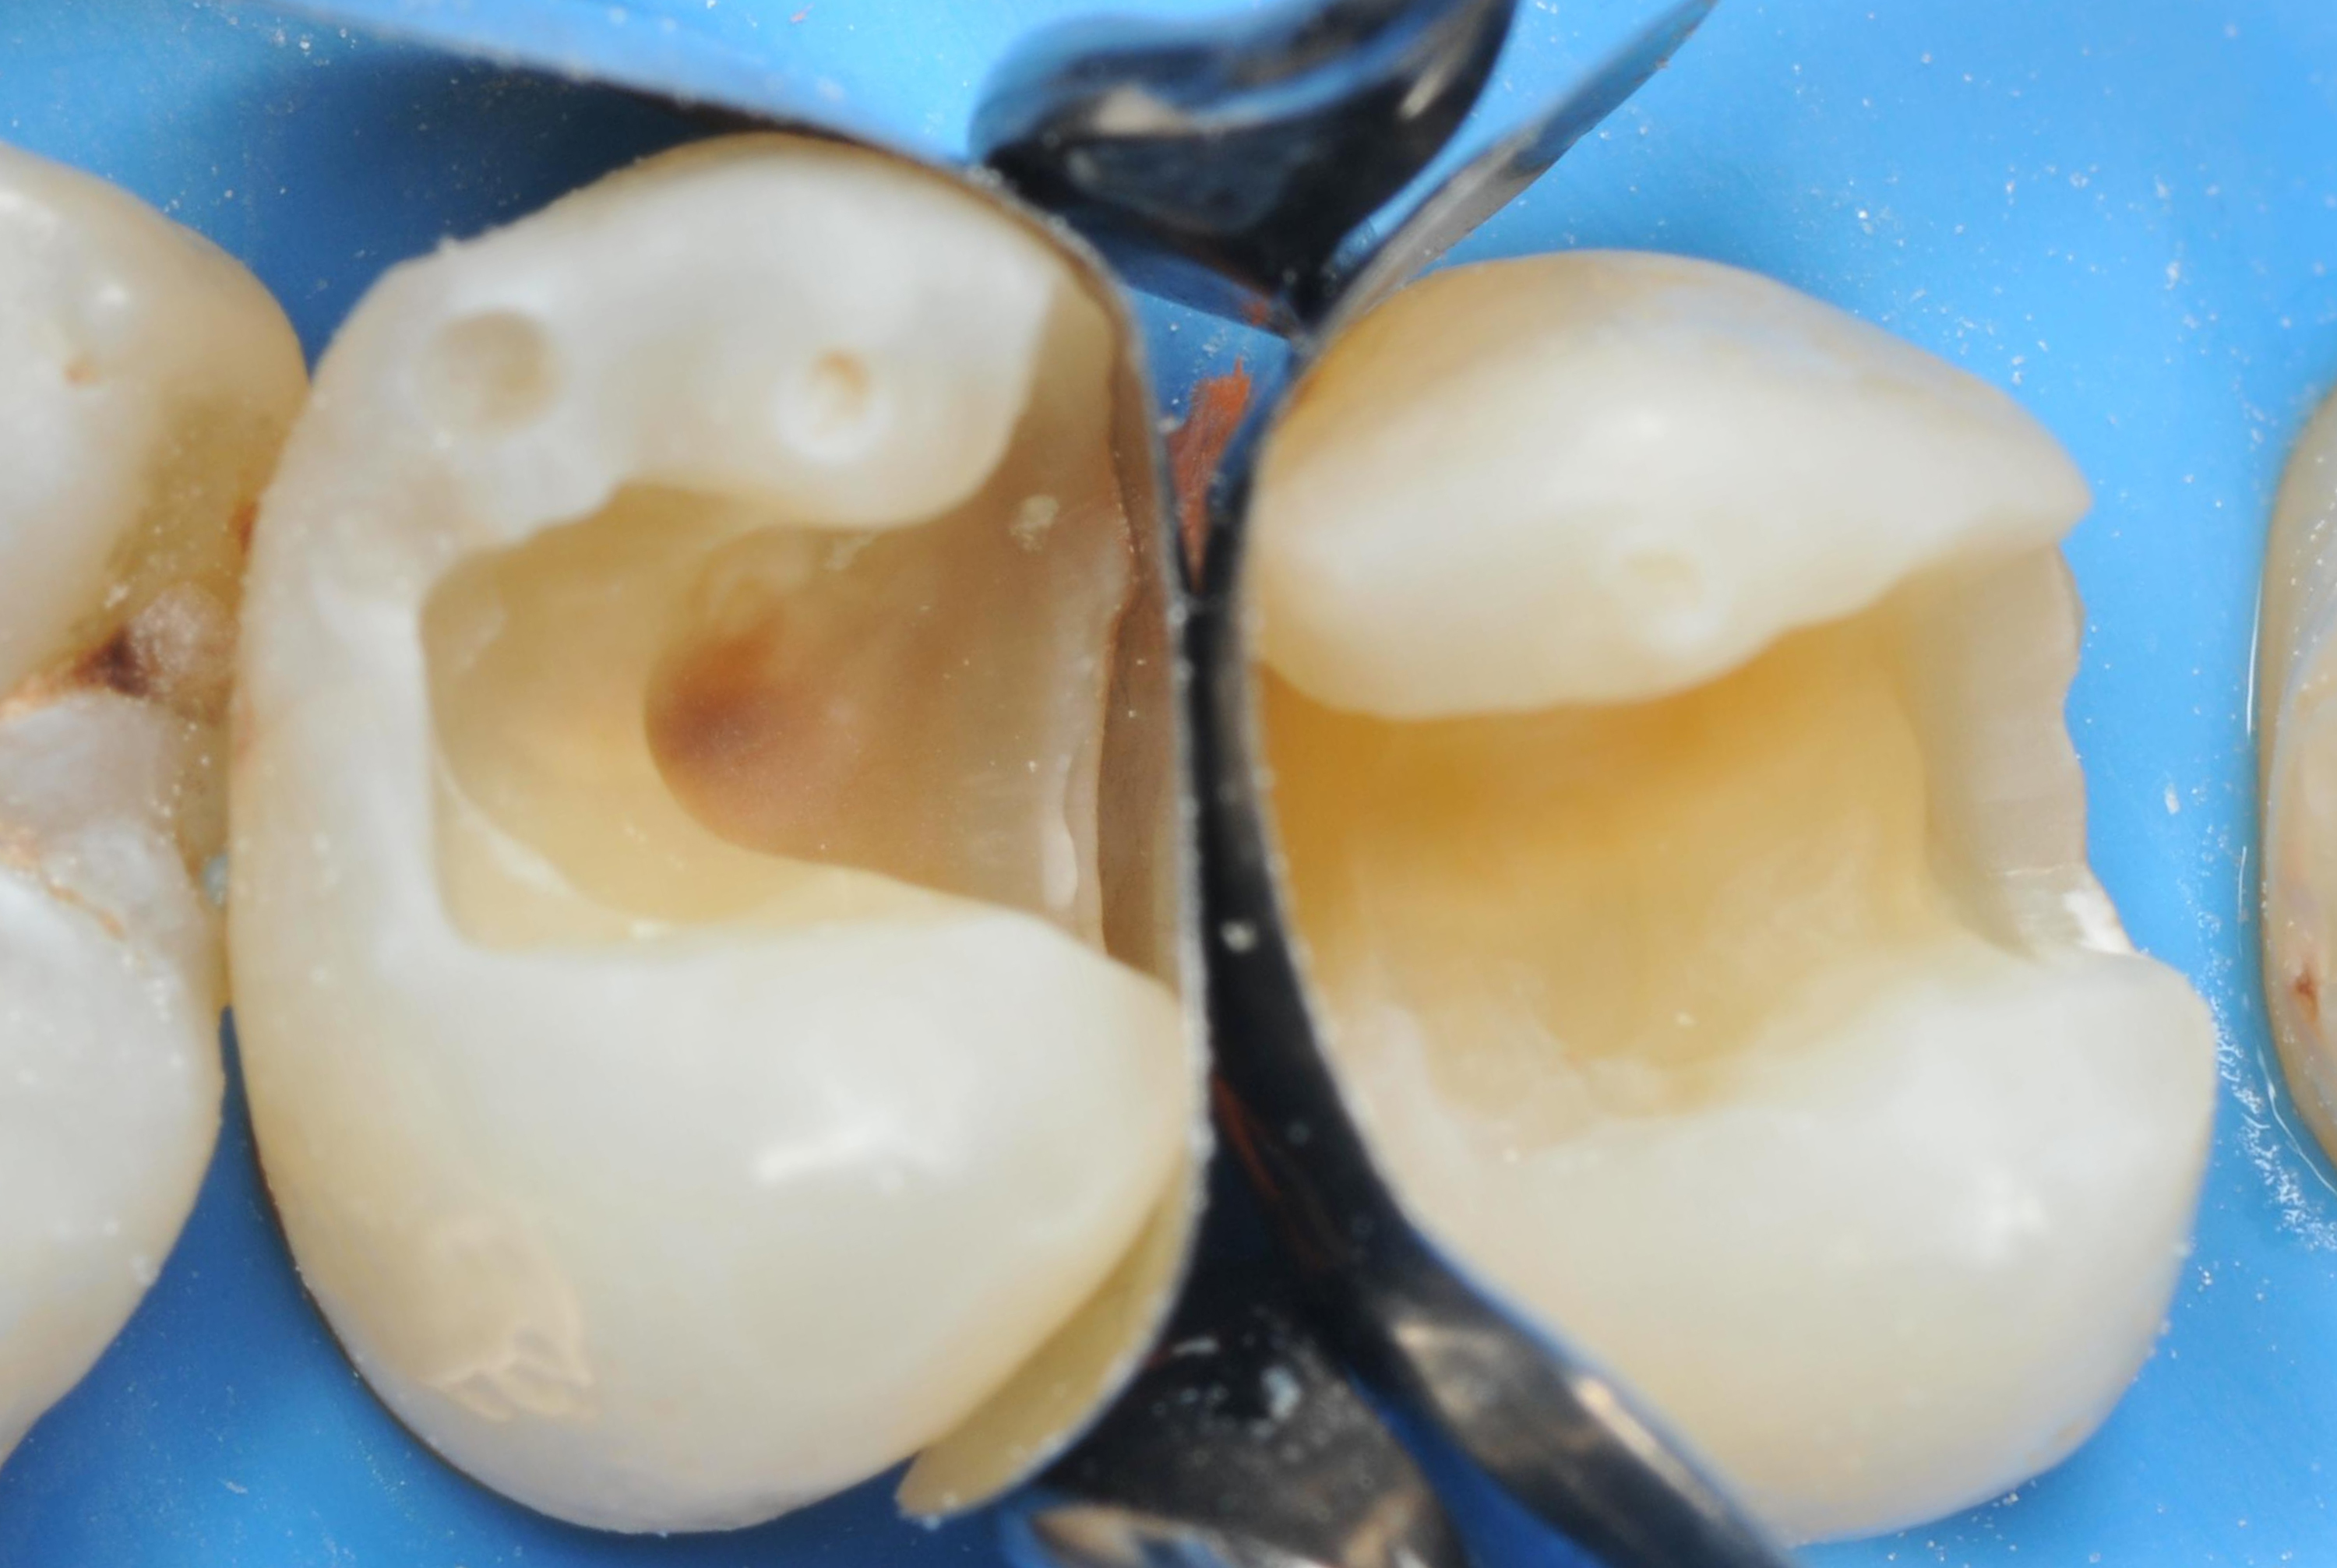

Po założeniu koferdamu usunięto stare wypełnienia i uzyskano dwa ubytki klasy II (ryc. 2).

Po przygotowaniu ubytków, do każdego z nich umieszczono dwie sekcyjne matryce, aby uzyskać jak najściślejszy kontakt, a następnie zabezpieczono je pomarańczowym drewnianym klinem (ryc. 3).